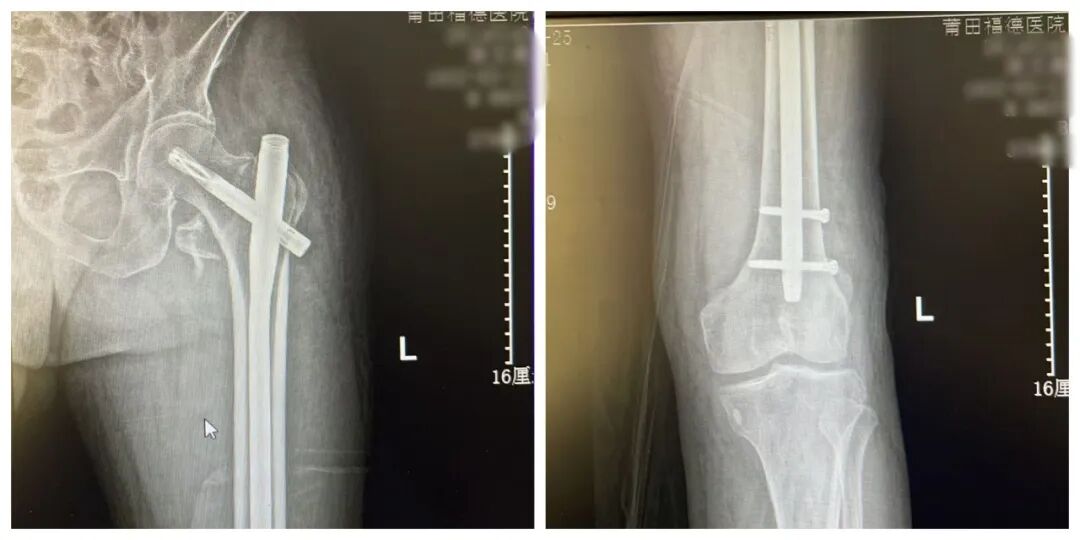

患者术后影像

手术过程顺利,术后 复查DR ,显示 断端对位良好,金属内固定在位, 手术效果满意。